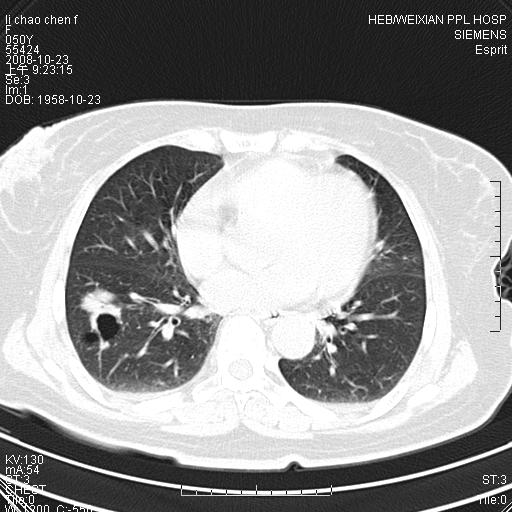

体检发现肺部肿块,现无不适。五年前曾有过哮喘病史。

先对现有的图象资料谈几点看法:病变位于右肺下叶前基底段,上部呈类圆形改变,分叶及毛刺征象不明显,下部呈不规则气腔改变,近肺门侧可见与一粗大血管相连,考虑为引流静脉影.其他肺叶相对正常所见.分析:该病灶良恶性均有可能.(现有资料来说).强化及穿刺活检有助鉴别.

考虑右肺下叶前基底段周围型肺癌可能性大。

右肺下叶前基底段占位性病变,不排除周围型肺癌可能,尽快手术为妙。

右肺下叶前基底段周围型肺癌可能性大。